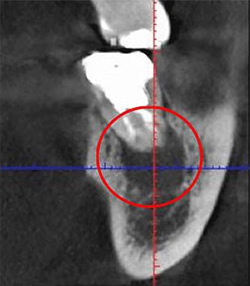

根管治療は通常の治療よりも非常に繊細な治療となります。下の画像をご覧ください。

黒くなっている部分が処置すべき部分となります。これらは肉眼だけではどうしても対応できません。目で確認できる限界があるためです。

しかし「高倍率ルーペ」を利用すると、これらをしっかり目で確認した状態で治療を進められます。どのくらい視野を拡大できるのかは、下記をご覧ください。肉眼と高倍率ルーペの視野の比較となります。

先にご紹介した、歯の黒い部分を取り残してしまうと再発の可能性が高まります。

それを防ぐためにも「精密さ」を追求した拡大治療は必須と言えます。